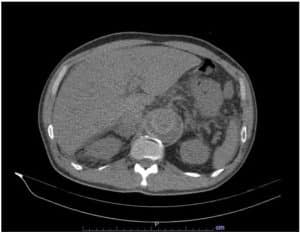

The patient was initially given paracetamol 1 gram, then tramadol 50 mg TIV, eventually nalbuphine 2 mg TIV because of intractable pain. At that time, the emergency physician was considering myositis vs. vascular occlusion. Routine labs were done. ECG revealed sinus rhythm, T wave inversion at V5-6, AVL, and lead 1. CBC showed leukocytosis with neutrophilic predominance. Chest x-ray revealed progression in the degree of mild pulmonary congestive changes as well as suspicion of concomitant pneumonia in the right lower lobe. Lumbosacral x-ray revealed a decompression deformity T 11. FPA supine and upright results were segmental adynamic ileus, which prompted consideration of hepatomegaly and lumbar osteophytosis. Hence, the patient was referred to Vascular (IM service) and TCVS for further evaluation and management. A Stat AV duplex scan was advised but not available in the ED. Hence abdominal CT scan (Figure 2 and Figure 3) with contrast and CT aortogram was performed. Tomography revealed atherosclerotic thoraco-abdominal aorta with mural thrombus formation, aneurysmal dilatation at the level of the ascending aorta, transverse arch, celiac artery, superior mesenteric artery, and renal artery, no dissection or contrast extravasation. Thus, the patient was then administered a heparin drip 10, 000 units in 100 cc to run for 10 cc/hr (18 units/kg/hr). Cefepime 2 g TIV as a loading dose for pneumonia was given as well.

Figure 2: Abdominal CT scan (axial view) showing extensive aortic occlusion

Imaging is an important tool in determining the location of the possible obstruction. In this case, thromboembolism was located at thoraco-abdominal aorta which led to an aneurysmal dilatation at the level of the ascending aorta, transverse arch, celiac artery, superior mesenteric and renal artery. These signs manifest as an abdominal pain in the patient.